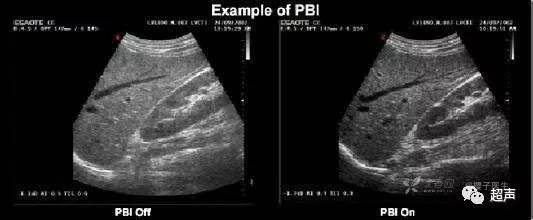

2、二维图片的灰阶适中

图像过亮或者过暗不仅很难看,而且会丢失更多的信息,灰阶的明暗以显示敏感区域最佳效果为原则,同时可以调节深度补偿增益TGC保持整幅图片近场、远场均匀一致。